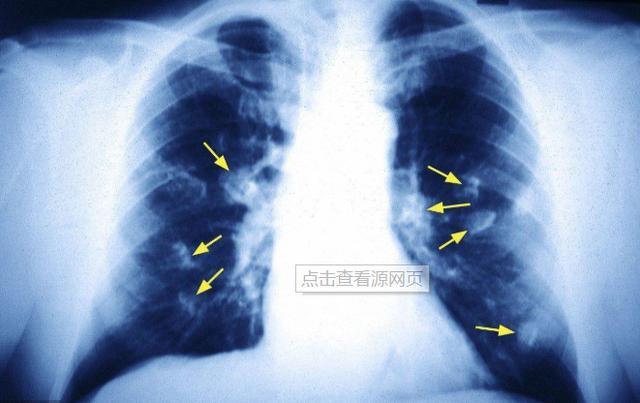

一、肺结节①恶性结节:恶性结节就是已经癌变的结节,是一定要手术切除的。这些恶性结节一般都是在影像学上表现为边缘不清、与周围的组织有黏连,有些牵拉胸膜,越不好的东西与周围越是不好分离。还有些可以呈现毛刺状、分叶状等不规则的形状。也有些边缘相对规则但是诚实性也属于恶性。对于一些典型的恶性肿瘤结节通过CT或核磁可初步诊断,对于病理检查结果为恶性的结节,只一定要切除的。因为在癌肿结节相对比较小的时候,进行手术切除配合一些辅助疗法是可以早期治愈的。

②实性肺结节直径>10mm:体积越大的结节恶变的可能性也越大。尤其是在定期随访中发现结节突然变大了一定要及时切除。③毛玻璃结节:这种结节提示恶性,肺部的恶性肿瘤很容易累及其他的器官,使多个器官功能受损,造成严重后果。良性的结节形状都比较规则,边缘也比较光滑,比较安全。而像毛玻璃样结节就比较危险了。